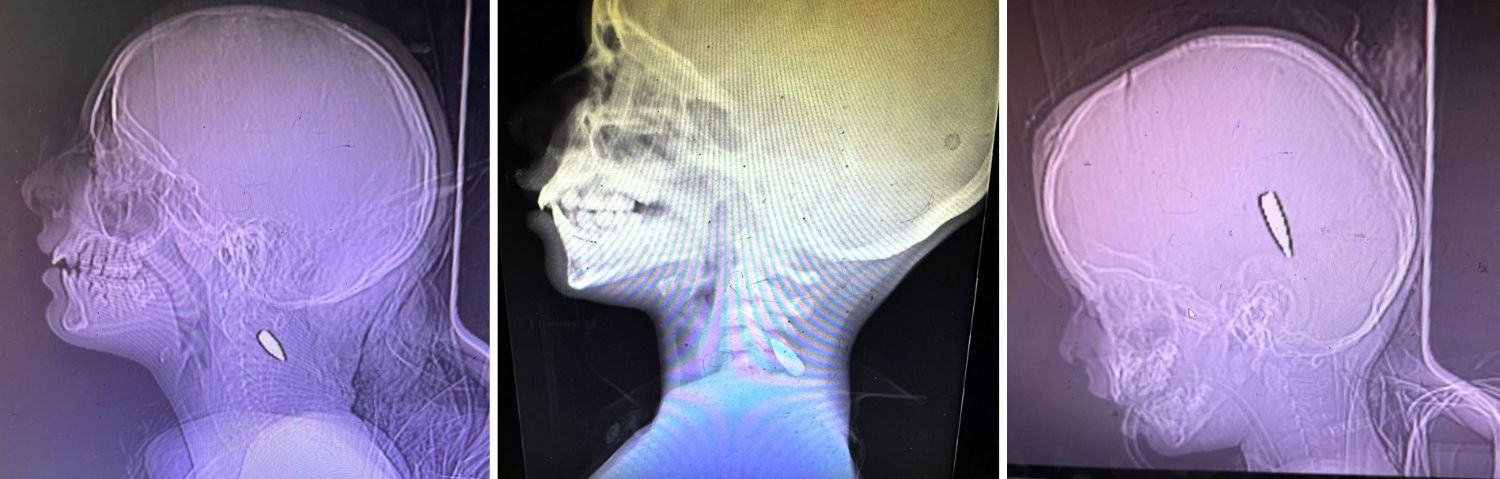

Two days ago, The New York Times -- which is usually supportive of U.S. and Israeli militarism -- did something very different. It extensively documented how the Israeli military is shooting little children in Gaza in the head and chest.